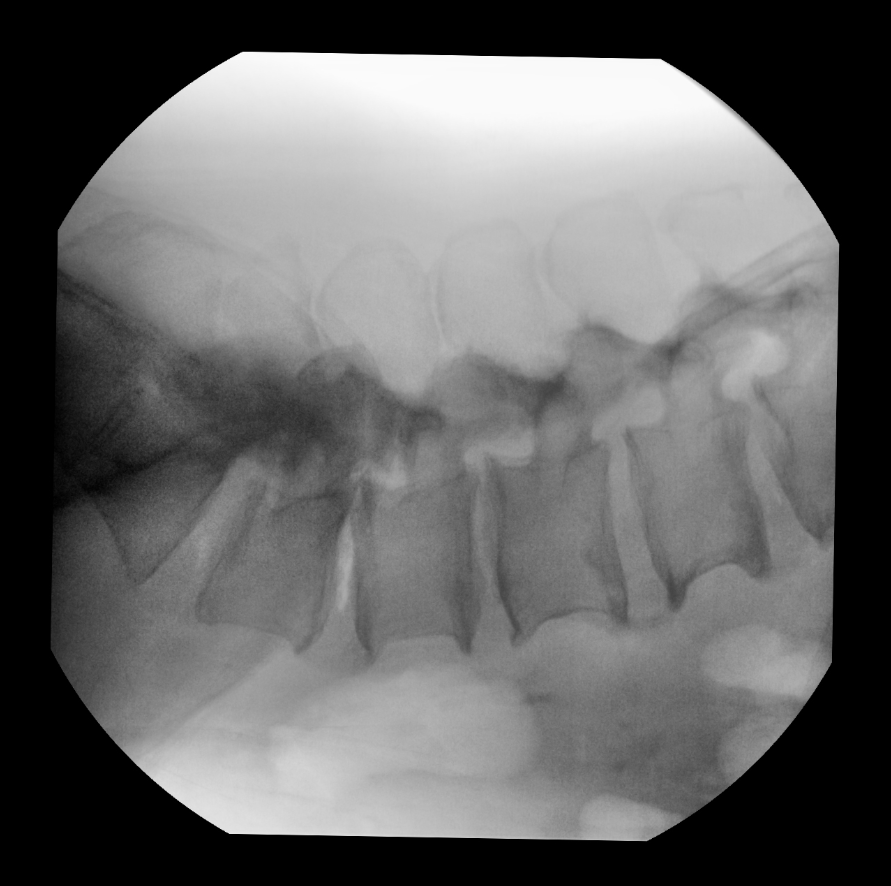

2D intraoperative imaging

Anatomical imaging profile is set to Spine. Fluoroscopy mode is set to standard continuous. A first fluoroscopic image is taken to confirm the vertebral level to treat. Further 2D imaging centering is done using the Live View camera of C-arm to limit the number of image acquisition and manage dose radiation level.

Lateral view – definition of incision level on L4

Antero Posterior view

Lateral View